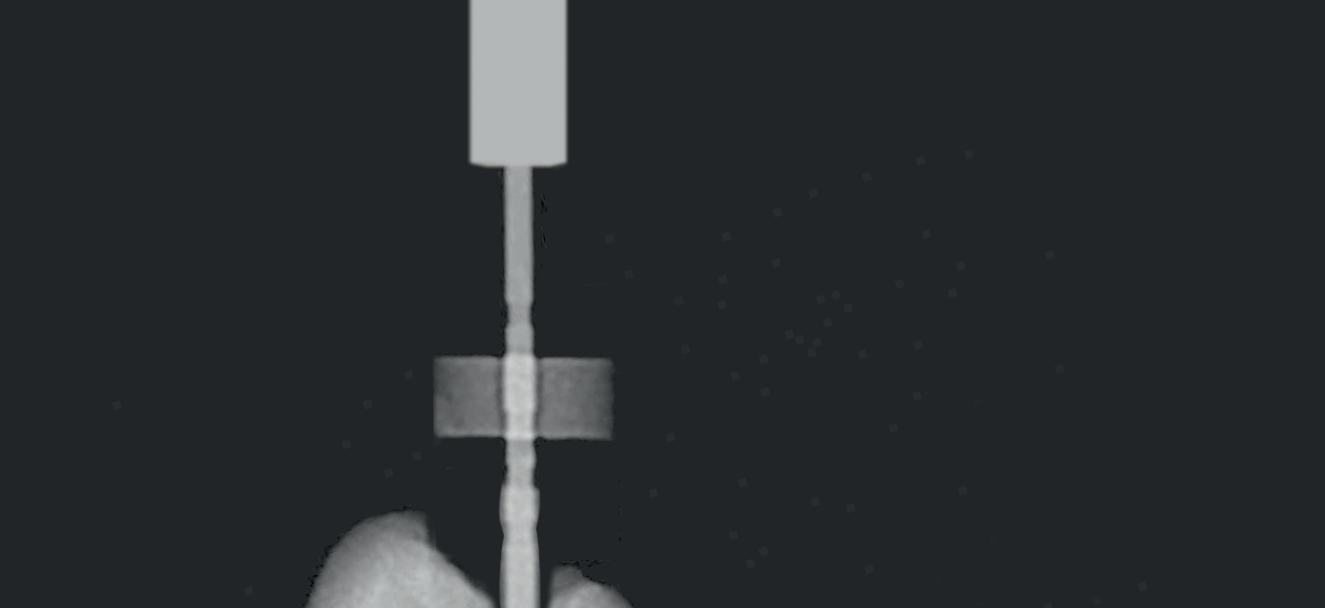

CCW CW CW CCW File example Mode Sequence CW CCW 3